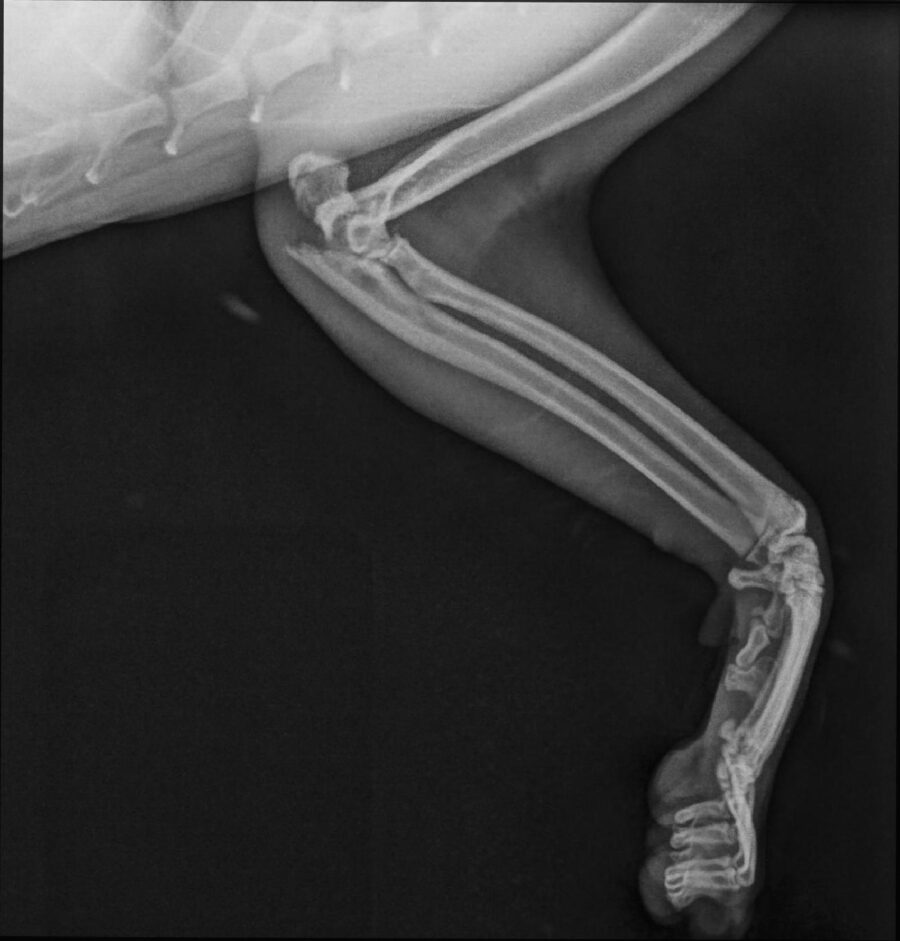

• Fracturen met platen, schroeven of pinnen

• Een te losse knieschijf opereren (patella luxatie)

• Kruisbandoperatie

• Heupkopresectie